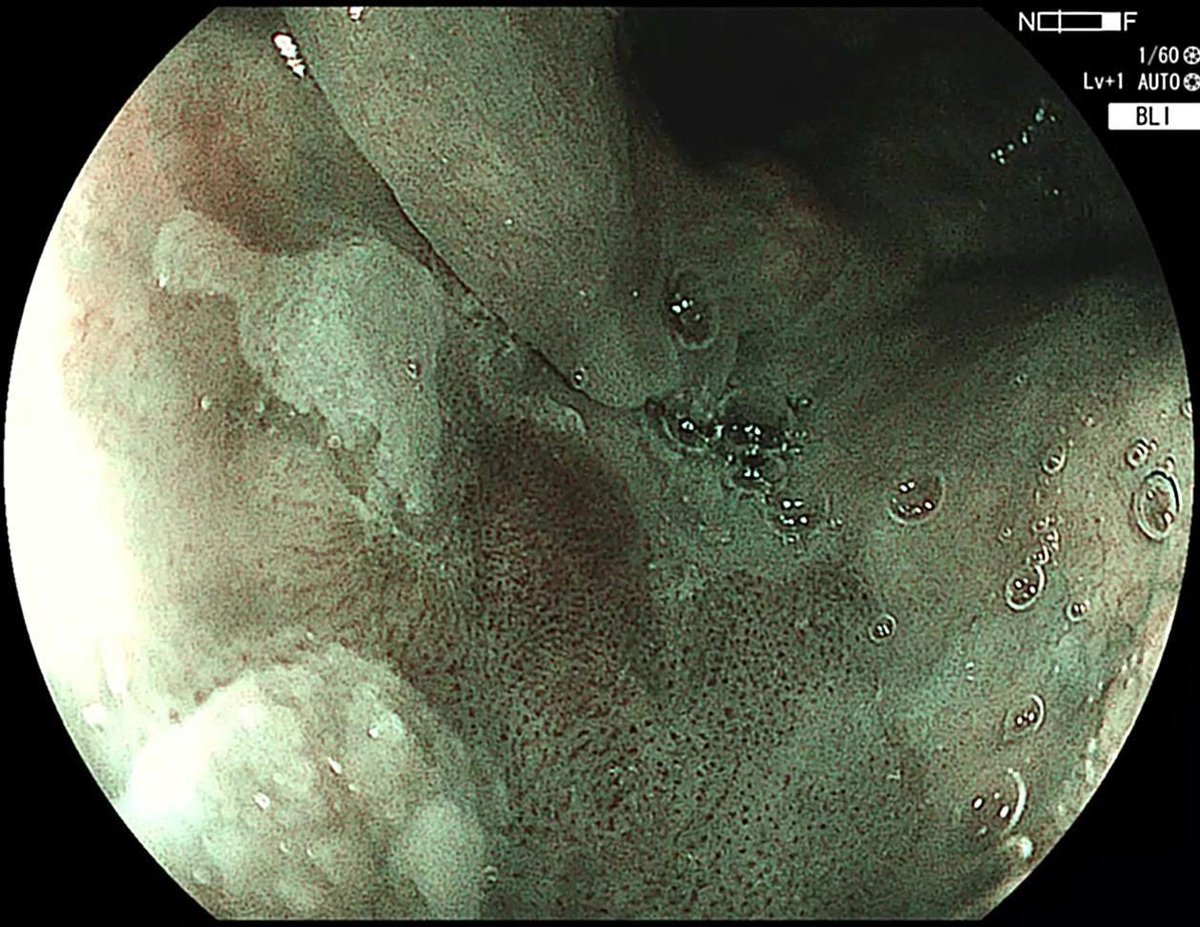

Delighted to share a MAJOR milestone in minimally invasive cancer treatment. We just completed the *first* Pharyngeal ESD in North America at @KingstonHSC . Huge thanks to the GI endoscopy team, @QueensuDOM, @SEAMOKingston for your endless support